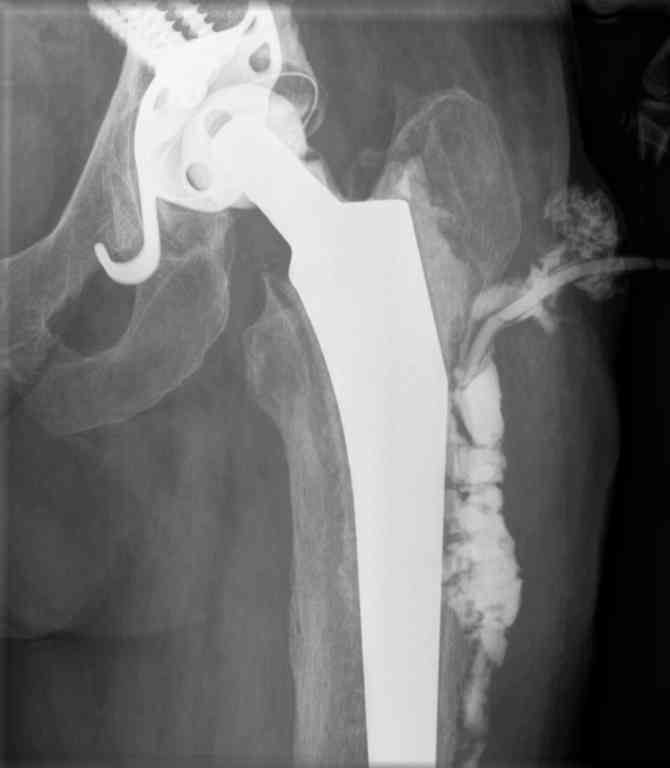

Подскажите, пожалуйста, варианты ревизии у пациентки 65 лет с нагноением эндопротеза т\б сустава.

В 2004 году установлен эндопротез с гладким п\о течением и заживлением раны. На протяжении всего времени больную беспокоили боли в области паха: бедра. Поступила с обстрением болевого синдрома и уже в отделении развился покожный абсцесс с формированием свища. Фистулография- в приложении.

Достаточно ли удалить протез и установить промывную систему или лучше спейсер? Если спейсер, тогда как дренировать костномозговой канал?